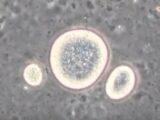

画像は「BBC」より引用子どもを作るためには精子と卵子が必要である、と我々は当然のように思い込んできたが、もしかするとそうではないのかもしれない――。そんな衝撃的なニュースを英BBCが報じている。

論文を発表したのは、英バース大学のトニー・ペリー氏らの研究チームだ。精子と卵子が受精して受精卵になる過程では、精子と卵子の遺伝子の役割が一度消される現象「リプログラミング(初期化)」が必要となる。これまで、この初期化を起こすためには卵子が必須と考えられてきたが、今回の論文は、その常識を覆した。なんと「卵母細胞」(成熟すると卵子になる細胞)を刺激して作成した単為発生胚に精子を導入したところ、精子の初期化が正常に行われ、健康な子どもが生まれることが世界で初めて確認されたのである。